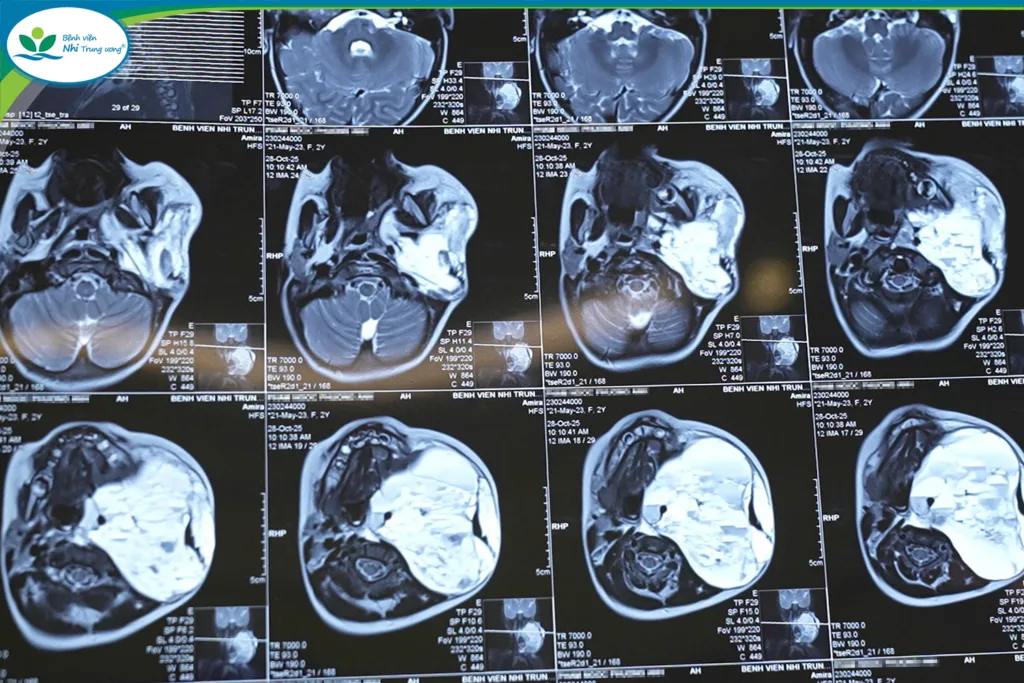

Khi được chuyển đến Bệnh viện Nhi Trung ương, tình trạng của bé P.A diễn biến rất xấu. Trẻ suy hô hấp nặng, phải đặt nội khí quản và thở máy hỗ trợ. Kết quả chụp cộng hưởng từ (MRI) cho thấy khối u kích thước “khổng lồ” (86x101x99mm), chiếm tới 3/4 vùng cổ, đang chảy máu cấp tính bên trong. Khối u chèn ép, đẩy lệch hoàn toàn thanh quản, khí quản và thực quản, gây hẹp lòng thanh hầu, đe dọa trực tiếp tính mạng trẻ do nguy cơ suy hô hấp, suy tuần hoàn và mất máu cấp.